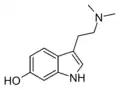

| Serotonin | Animals, plants | 5-OH | H | H | 5-hydroxytryptamine | 50-67-9 |

| Bufotenin | Animals, plants, fungi | 5-OH | CH3 | CH3 | 5-hydroxy-N,N-dimethyltryptamine | 487-93-4 |